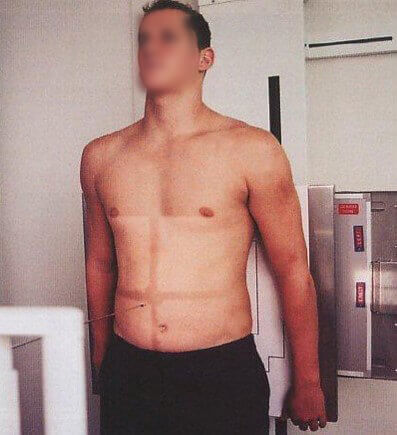

A hypersthenic person is a very muscular, thick-set individual, with a broad bony chest and high diaphragm. In this body type, the stomach tends to lie transversely and the gall-bladder horizontally high in the abdomen, well away from the midline. The transverse colon is also high, as well as the heart and the lungs.

A sthenic person is a muscular, thick-set individual similar to hypersthenic but not quite as broad in relation to height. The stomach and gall-bladder lie more vertically and the transverse colon curves lower.

On the other hand, the radiographer has to increase these technical factors for hypersthenic patients and to decrease them for asthenic patients to improve the image quality. Let’s see the difference in the image clarity below.